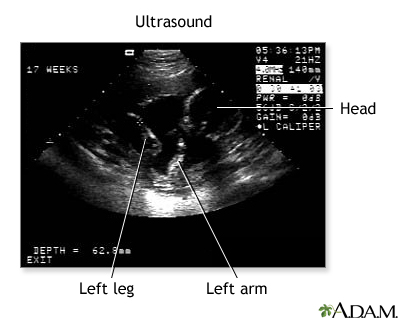

Ultrasound, normal fetus - arm and legs - illustration

This is a normal fetal ultrasound performed at 17 weeks gestation. This is the type of image pregnant mothers may see on the ultrasound screen, or that the technician may print. It shows the head on the right, and the cross hair pointing to the left ankle. The left leg and arm are visible in the center of the screen.

Ultrasound, normal fetus - arm and legs